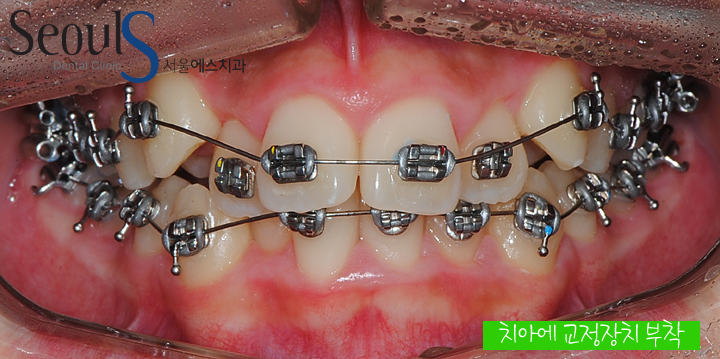

정면 치아 모습입니다

정면 치아 모습입니다

치아가 날 공간이 모자라 덧니가 났습니다

치아에 교정 장치를 부착하고

치아를 서서히 이동시키고 있습니다